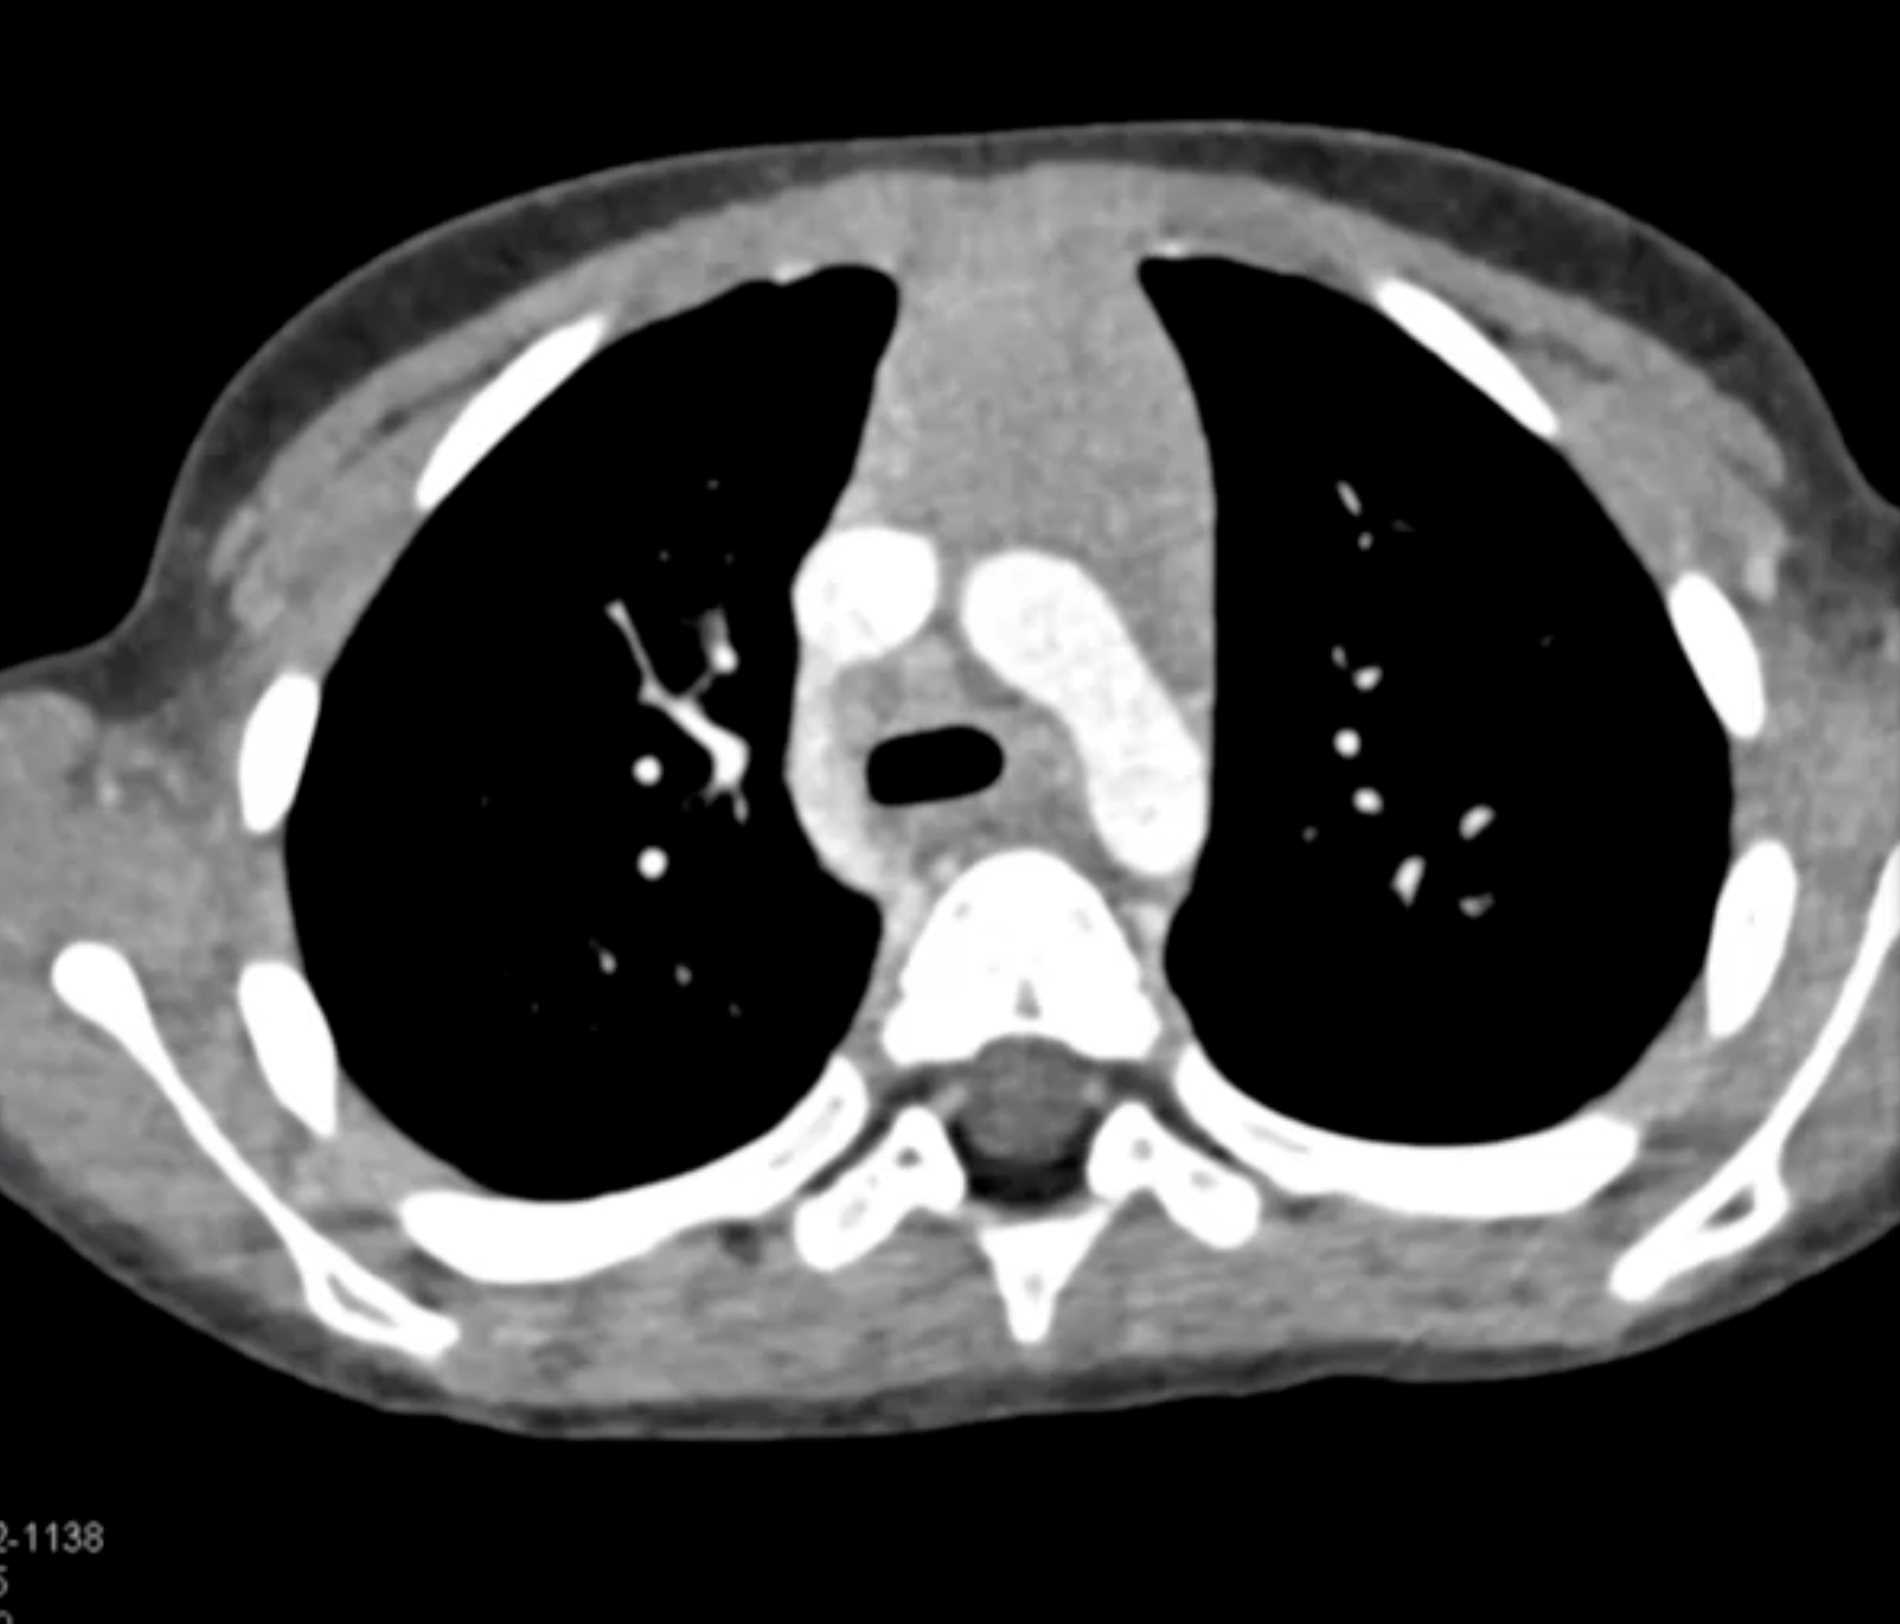

Hodgkin Lymphoma